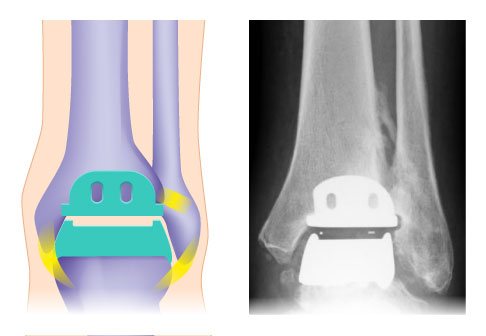

Rechts eine Zwei-Komponenten-Prothese mit fixiertem Inlay, links eine Drei-Komponenten-Prothese mit mobilem Inlay. © Gelenk-Klinik

Die Drei-Komponenten-Prothese ist im Vergleich zur Zwei-Komponenten-Prothese flexibler. Sie unterstützt die natürliche Biomechanik des Sprunggelenks, weil sie in alle Richtungen beweglich sind. Die Drei-Komponenten-Prothese kann bei stabilen und korrekten Achsverhältnissen knochensparend eingesetzt werden.

Die Zwei-Komponenten-Prothese erreicht eine höhere Stabilität, weil das Kunststoffinlay stabil im Schienbein fixiert wird. Diese Prothese eignet sich besonders bei einem sehr instabilen Sprunggelenk. Da der Spezialist das Inlay in höherer Lage im Knochen befestigt, muss er bei diesem Eingriff mehr Knochengewebe entfernen.

2-Komponenten-Sprunggelenksprothese mit fixiertem Inlay links. Rechts ist die 3-Komponenten-Sprunggelenksprothese abgebildet. Sie besitzt mit dem mobilem Inlay zusätzlich zur Schienbein- und Sprungbeinkomponente eine eigenständige dritte Komponente.

Schema und Röntgenkontrolle einer individualisierten Sprunggelenksprothese (OSG-TEP) von vorne. Zwischen den beiden Metallkomponenten liegt das Inlay, welches für die radiologische Kontrolle der richtigen Lage durch einen Metallmarker markiert ist (links). © Gelenk-Klinik